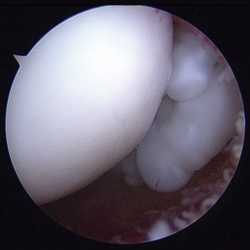

Con el diagnóstico de condromatosis sinovial de hombro derecho se procedió a la realización de una artroscopia, viendo múltiples cuerpos libres intraarticulares, la mayoría de ellos de consistencia cartilaginosa (Figuras 3 y 4) y se procedió a su extracción por vía artroscópica (Figura 5). Tras la cirugía, se remitió a la paciente a recuperación funcional, presentando una buena evolución clínica. La paciente se encuentra asintomática en el momento actual, presentando un balance articular completo.

Figura 5. Exéresis de cuerpos libres.